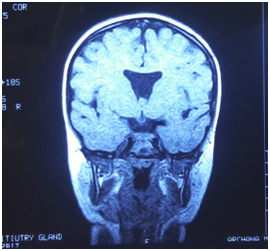

2 years old male, product of non-consanguineous union presented with rapid gain in weight, not recognising parents and surroundings and global developmental delay and behavioural problems in our clinic. Birth history was uneventful apart from physiological jaundice. There was no history of seizures, polyuria and temperature instability. On examination his weight was 24kgs (Z score+5.47), length was 89.5cms with BMI of 30.3kg/m². He had mild dysmorphism in form of epicanthic fold, low set ears and depressed nasal bridge. Opthalmological examination showed right eye squint and nystagmus (Figure 1-4). Fundus showed optic disc hypoplasia (Right>Left). Hormonal evaluation showed normal free T4 (1ng/dl), Serum cortisol -12.5ug/dl, Serum prolactin - 22ng/ml. Fasting blood glucose, electrolytes and lipid profile were normal. In view of global developmental delay and optic atrophy neuroimaging was performed with showed absence of septum pellucidum, hence confirming the diagnosis. He was managed with lifestyle modification, behavioural therapy and regular monitoring for endocrinopathies.

Figure 1 Coronal section of MRI Brain showing absent septum pellucidum (Thin arrow) and hypoplastic pituitary (Bold arrow).